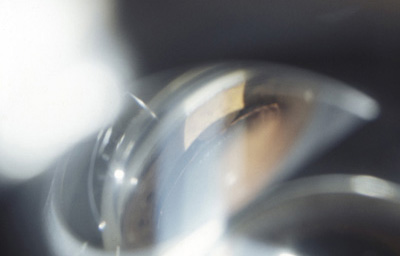

Melanoma sólido nodular del Iris con lente de Gonioscopía

Archivo Fotográfico Dr. Francisco Barraquer.